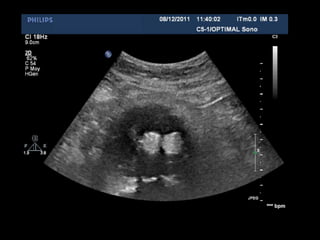

Aspect normal: 2D transverse

Aspect normal: Doppler